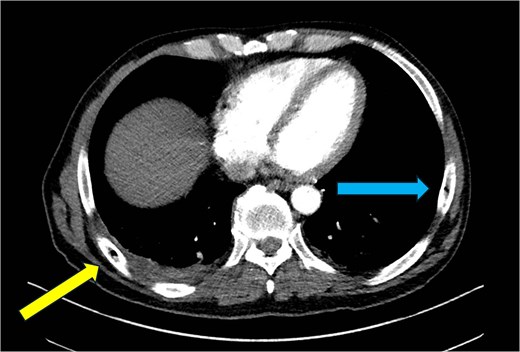

CT chest—axial plane. Intraosseous gas visualized in the right sixth rib (yellow arrow, left) and left seventh rib (blue arrow, right).